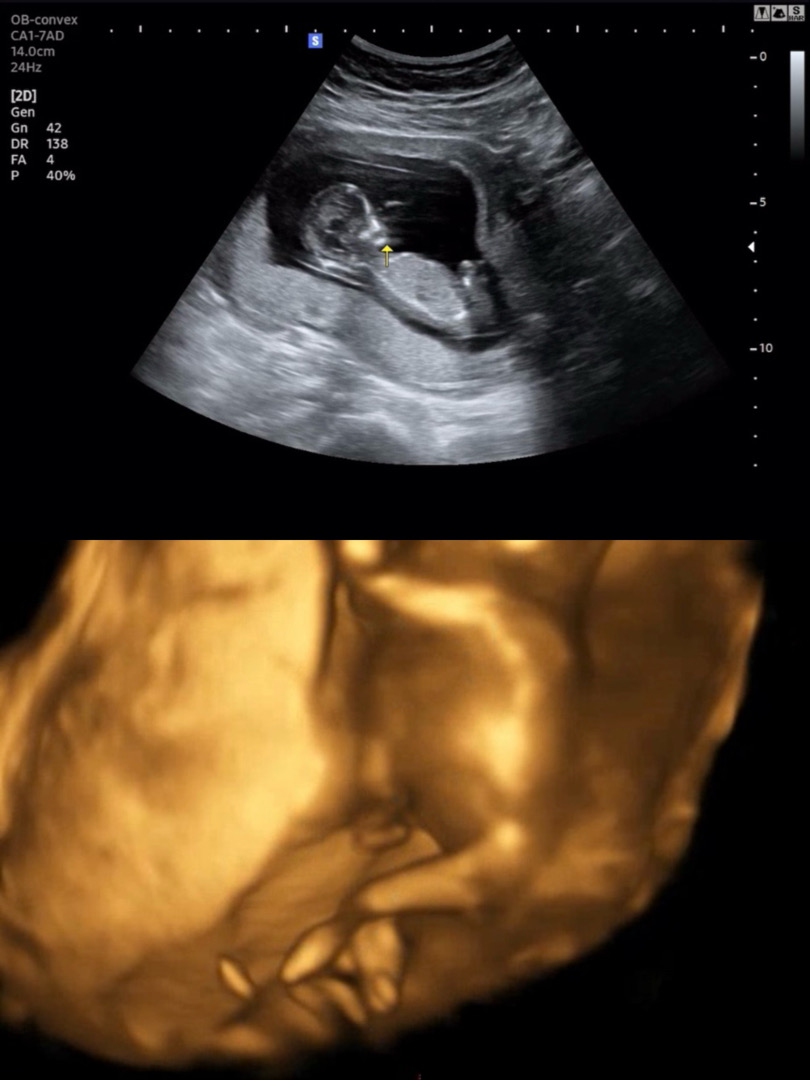

이걸로도 성별을 알 수 있을까요..? 도와주세용...

각도법이나.. 등등 성별을 알 수 있을까요? 도와주세용... 너무 궁금하네요🥹

생식기부위가 잘 안보여요 ㅠ 각도법은 입초로는 볼 수 없어요 ㅠ

흠.. 저는 여자일거같아요